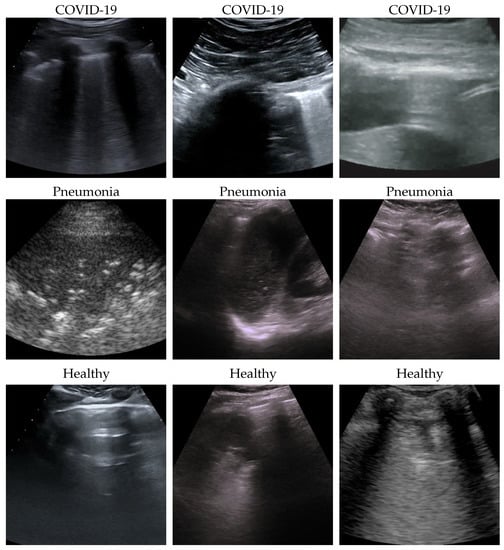

The dataset used for this task is, to our knowledge, the largest publicly available LUS dataset [39], comprising a total of 261 ultrasound videos and images from 216 different patients among 41 different sources. The data were collected, cleaned, and reviewed by medical experts. In particular, for the sake of this work and comparability with the SOTA, we used the frame-based version when every single frame of each video is classified. In Table 1, data distribution is described, and in Figure 1, some examples for each class are shown. More details about the whole dataset (e.g., patient distribution, acquisition technique, sources) are described both in [1] and in the GitHub repository of the project.

Figure 1. Some COVID-19 (first row), pneumonia (second row), and healthy (third row) samples from the dataset. As can be appreciated from the images, even among the same class, the sample appears to be very heterogeneous, and there is no kind of bias (e.g., pattern, color).